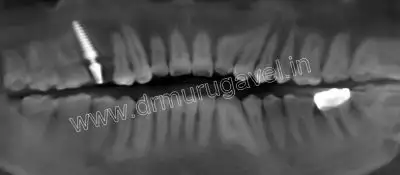

Day-1

Post implant x-ray

- prophylactic medicines given

- Local anesthesia given using STA

- Flap less implant placed in 15 region

- Intra oral scanning done using digital scanner